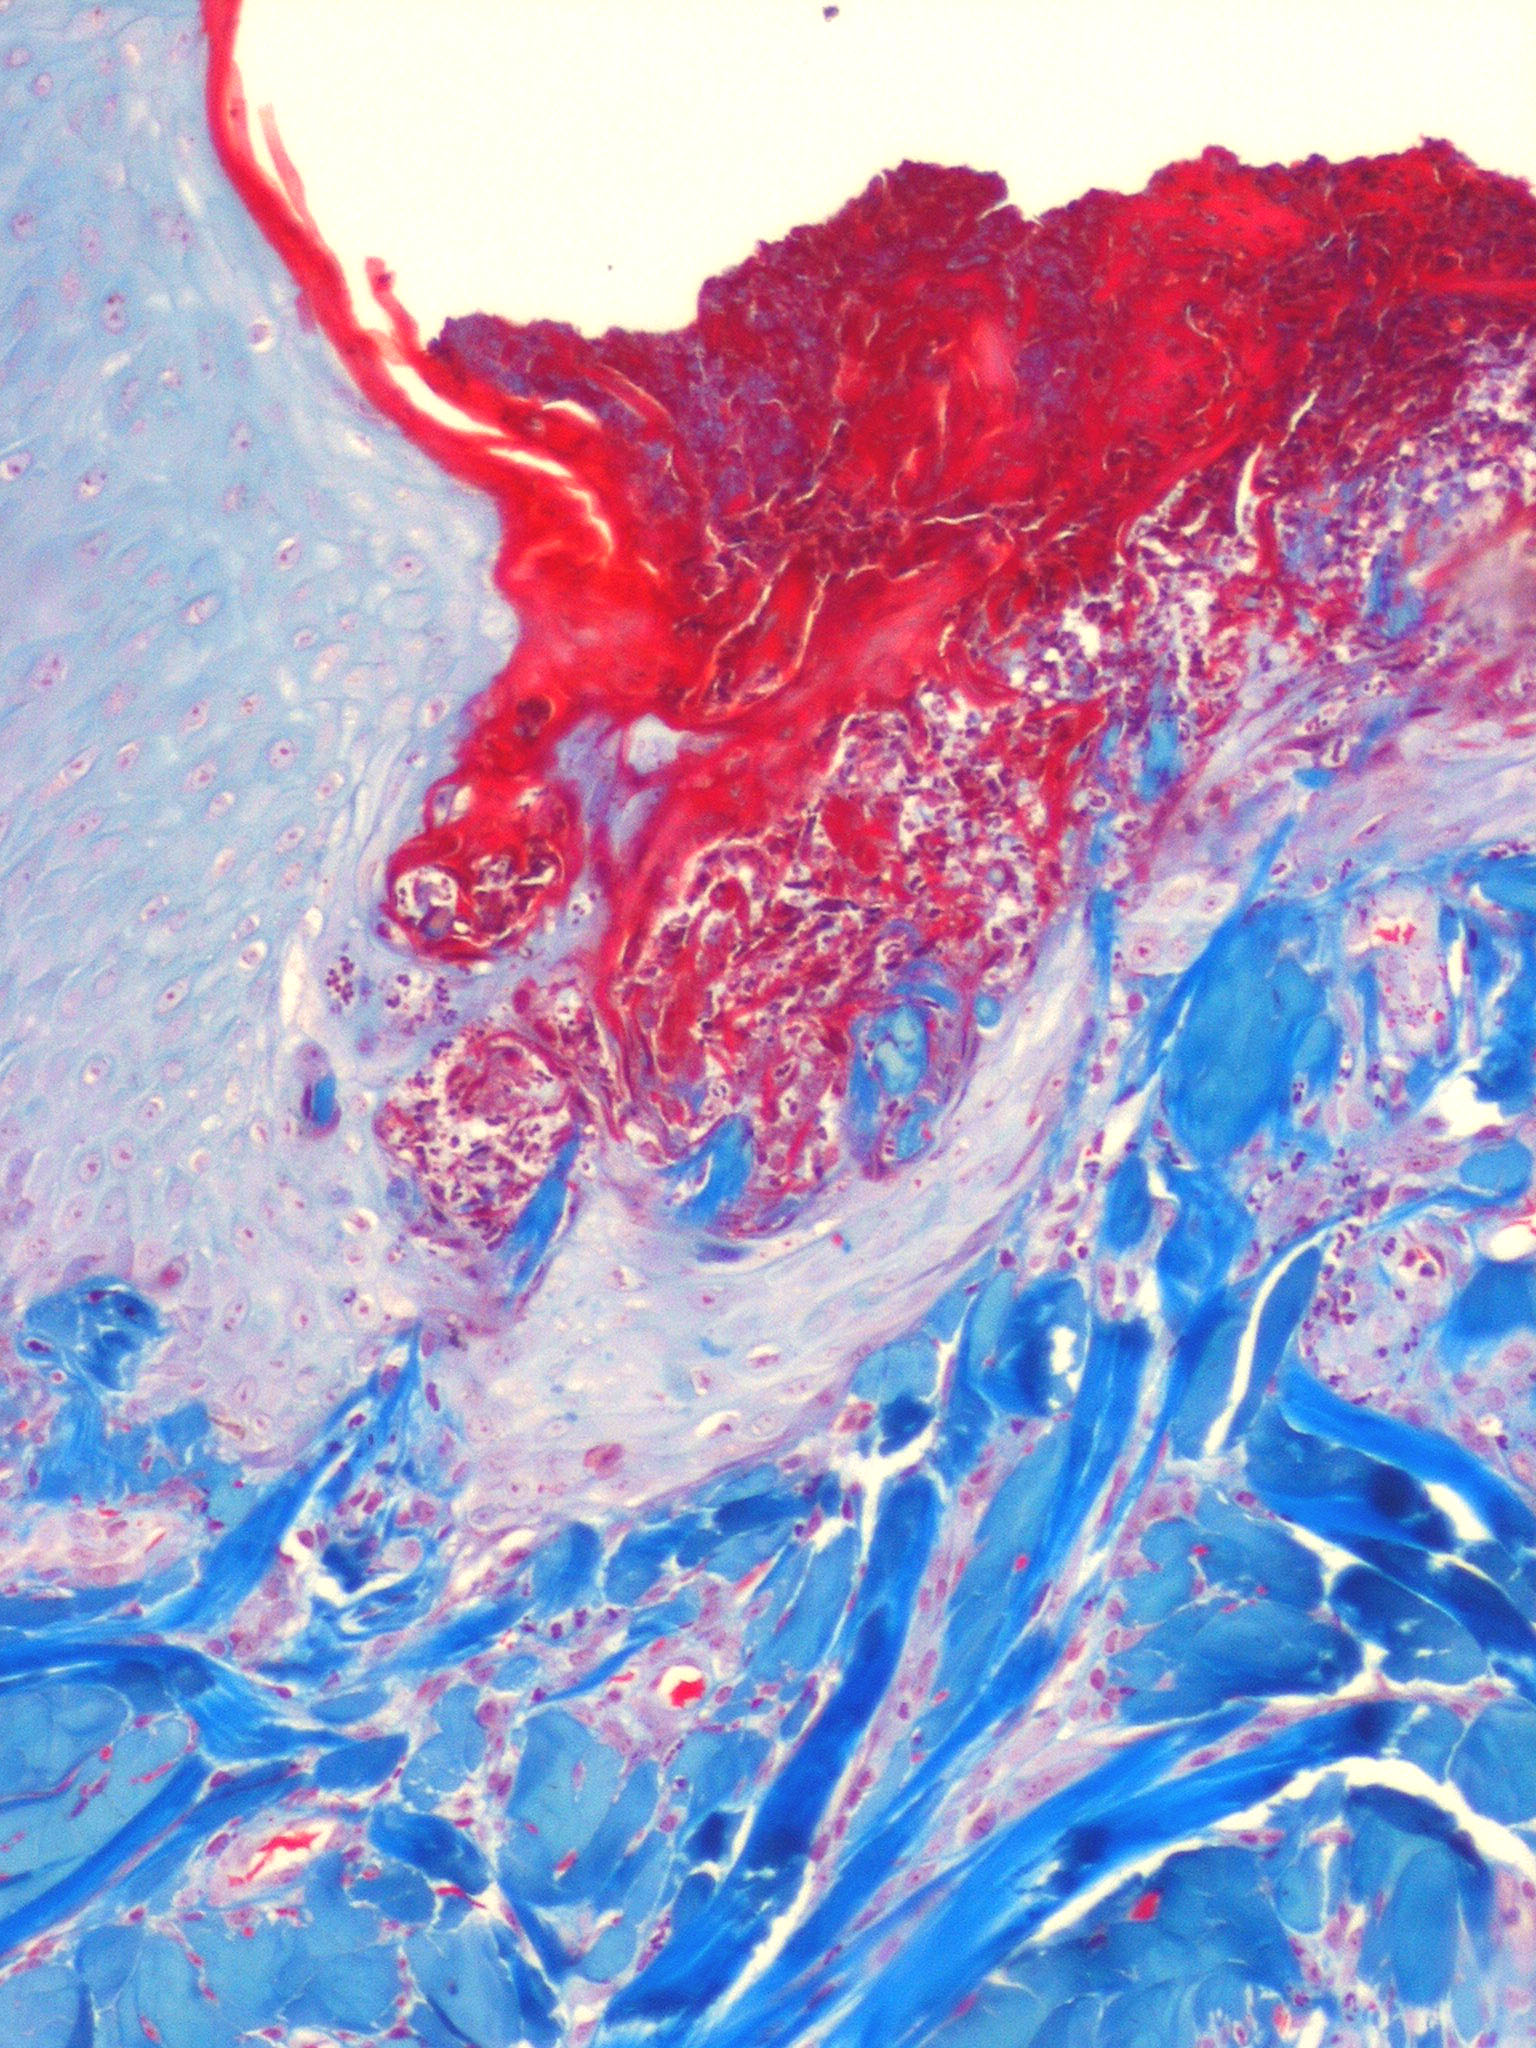

The histology varies with the stage of the reactive perforating collagenosis. Early lesions show epidermal hyperplasia associated with underlying degenerate basophilic collagen fibers. In established lesions, a cup-shaped depression of the epidermis associated with a keratin plug containing parakeratosis, inflammatory debris and collagen fibers can be seen.

Vertically orientated basophilic collagen fibers are seen in the underlying dermis, with focal extrusion through the epidermis

The epidermis is atrophic and may show ulceration. However, at the edges of the cup-shaped invagination, the epidermis is hyperplastic. Additionally, a mild perivascular lymphohistiocytic infiltrate can be seen.

Extruded collagen fibers may be demonstrated with elastic van Gieson (EVG) staining, which stains the fibers red. No extrusion of elastic fibers should be seen (staining black with EVG).